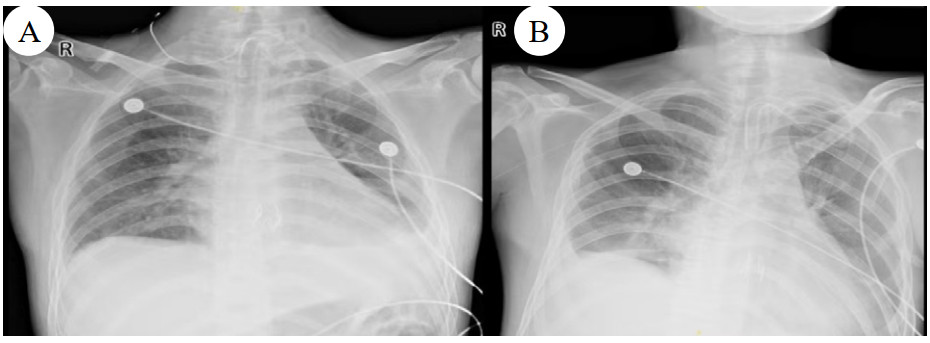

| 注:图A为B某;图B为C某 图 5 患者病变肺组织 |

| 注:图A为B某;图B为C某 图 6 患者肺移植术后胸片 |